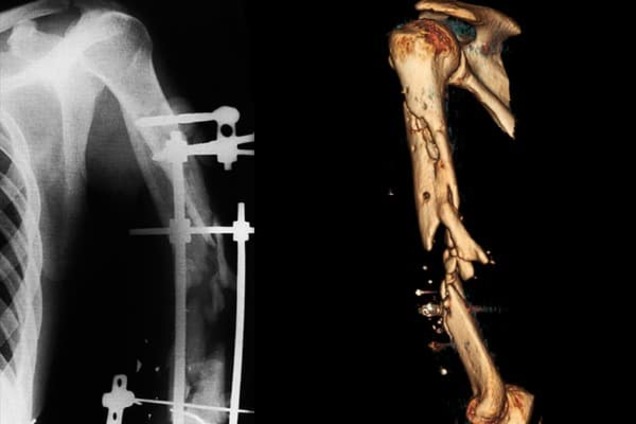

Українські лікарі виростили 15 сантиметрів кістки, щоб врятувати від інвалідності бійця АТО

Без застосуванням біотехнологій молодому бійцю загрожувала інвалідність, як зазначили волонтери